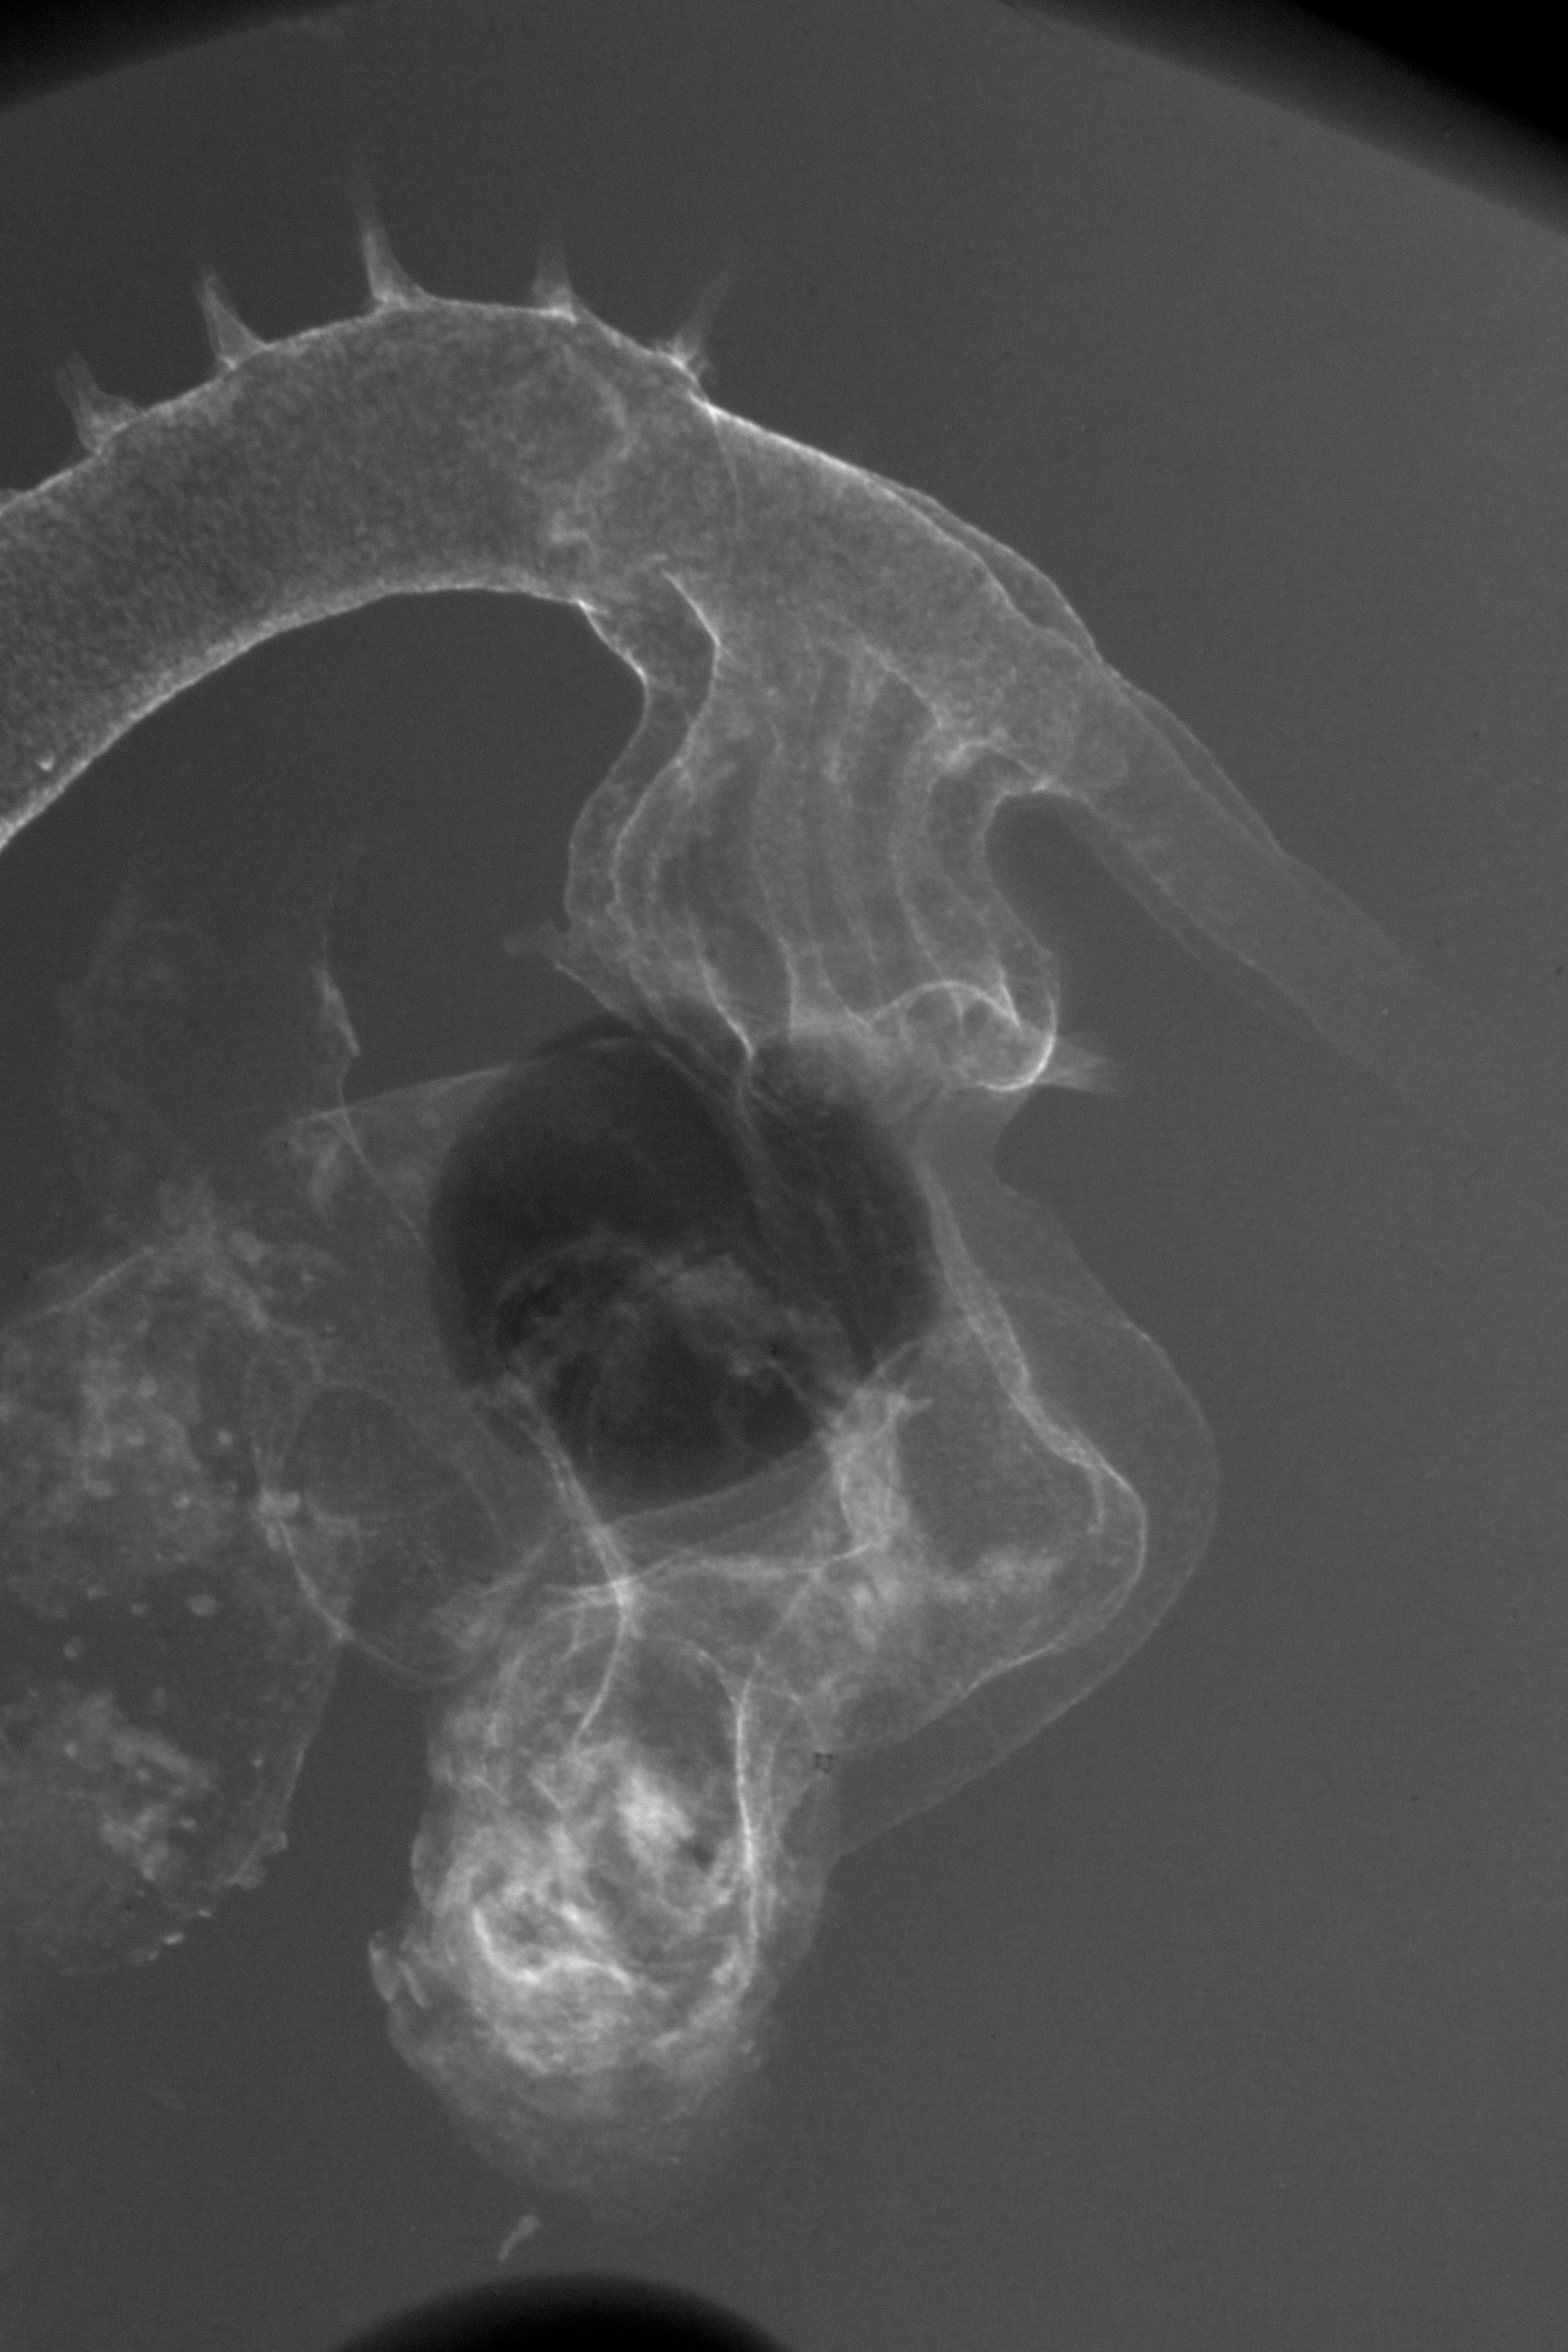

Chick Embryo Microangiography

Hamburger-Hamilton (HH) Stage 21 (approx. 3.5 days)

Stereo X-Ray Micrographs